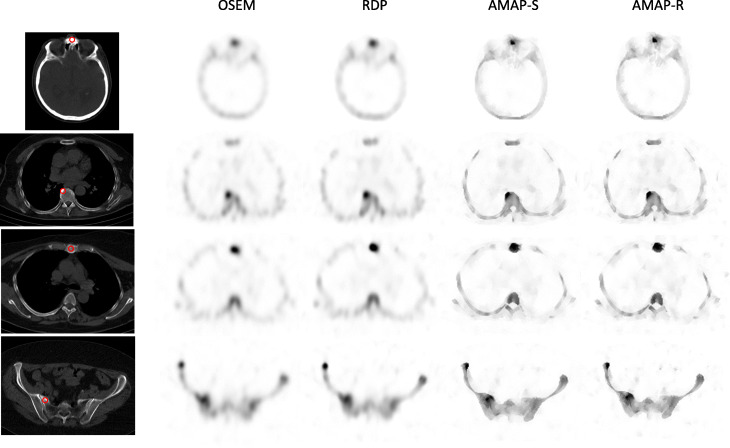

Fig. 7.

Example transversal slices of four lesions from clinical patient studies. The red circle presents the VOI used to analyze the studies. The color scale is set to SUV 15 for all images

The number of lesions and normal uptake samples for each area is listed in Table 4. Table 5 shows SUVs for the lesions, Table 6 for normal uptake areas, and Table 7 for SUVR, which was defined as the ratio of lesion and normal uptake SUVs. Tables 5 and 7 show that Bayesian methods offer higher SUVs than OSEM also with clinical patient data. For SUVmax, the RDP method gives 16 ± 9% higher values than OSEM, while AMAP-S and AMAP-R offer increases of 36 ± 8% and 36 ± 9%, respectively. With regard to SUVmean RDP, AMAP-S and AMAP-R offer increases of 18 ± 9%, 26 ± 5%, and 33 ± 5%, respectively. These differences to OSEM are statistically significant (Wilcoxon signed rank test), with all p values less than 0.001. Figures 6 and 7 show example images of clinical patient studies. Figure 6 shows example maximum intensity projections (MIP) of two clinical patients, while Fig. 7 shows example transversal slices of two lesion areas for the same two patients. AMAP-S and AMAP-R images clearly show more anatomical detail when compared to OSEM or RDP.

AMAP-S and AMAP-R reconstructions with matching CT lesions produce the most accurate results (Table 2) especially in terms of SUVmean. They preserve the correct lesion size and shape (Figs. 2 and 3). The appearance of lesions is overall quite different with AMAP-S and AMAP-R when compared to OSEM or RDP (Figs. 6 and 7). Reconstructions with anatomical prior information force bone lesions in SPECT images to follow bones and not to extend outside the bone boundaries (Fig. 7).